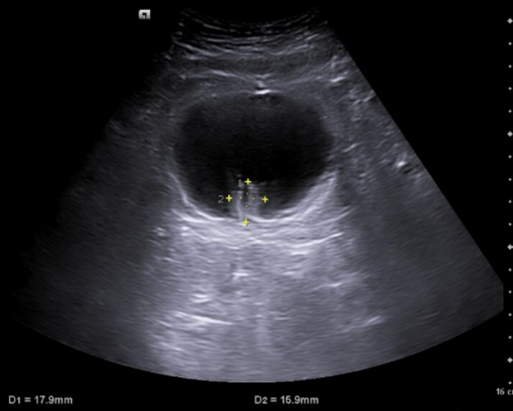

En ecografía clínica de aparato urinario se objetiva a nivel de vejiga imagen hiperecogénica dependiente de pared que no se moviliza con la movilización del paciente y no capta con modo Doppler color.

Ecografía aparato urinario agosto 2024: Litiasis en cáliz medio izquierdo de 6 mm, lesiones vesicales, próstata de 45 g.

Cistoscopia agosto 2024: Descripción de hallazgos vesicales: Lesión papilo-sólida en fondo vesical con calcificaciones en su superficie, de aproximadamente 1-1,5 cm de tamaño.